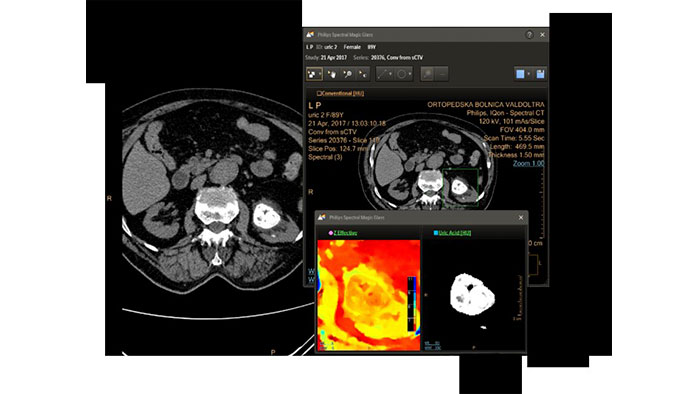

Spectral Light Magic Glass

CT Spectral Light Magic Glass

Review spectral data in a range of not spectral-enhanced CT applications

Allows retrospective use of spectral data that was saved in a series of spectral base images (SBI).

The fast launch of LMG allows review and identification of the most relevant results to be launched into the application for further analysis.

Benefits

• The option is available from the following applications: Brain Perfusion, Functional CT, Liver Analysis, PAA, TAVI, Acute Multifunctional Review, Virtual Colonoscopy.

• Spectral Magic Glass can be launched only for CT images or images created on the Philips IQon Spectral CT.